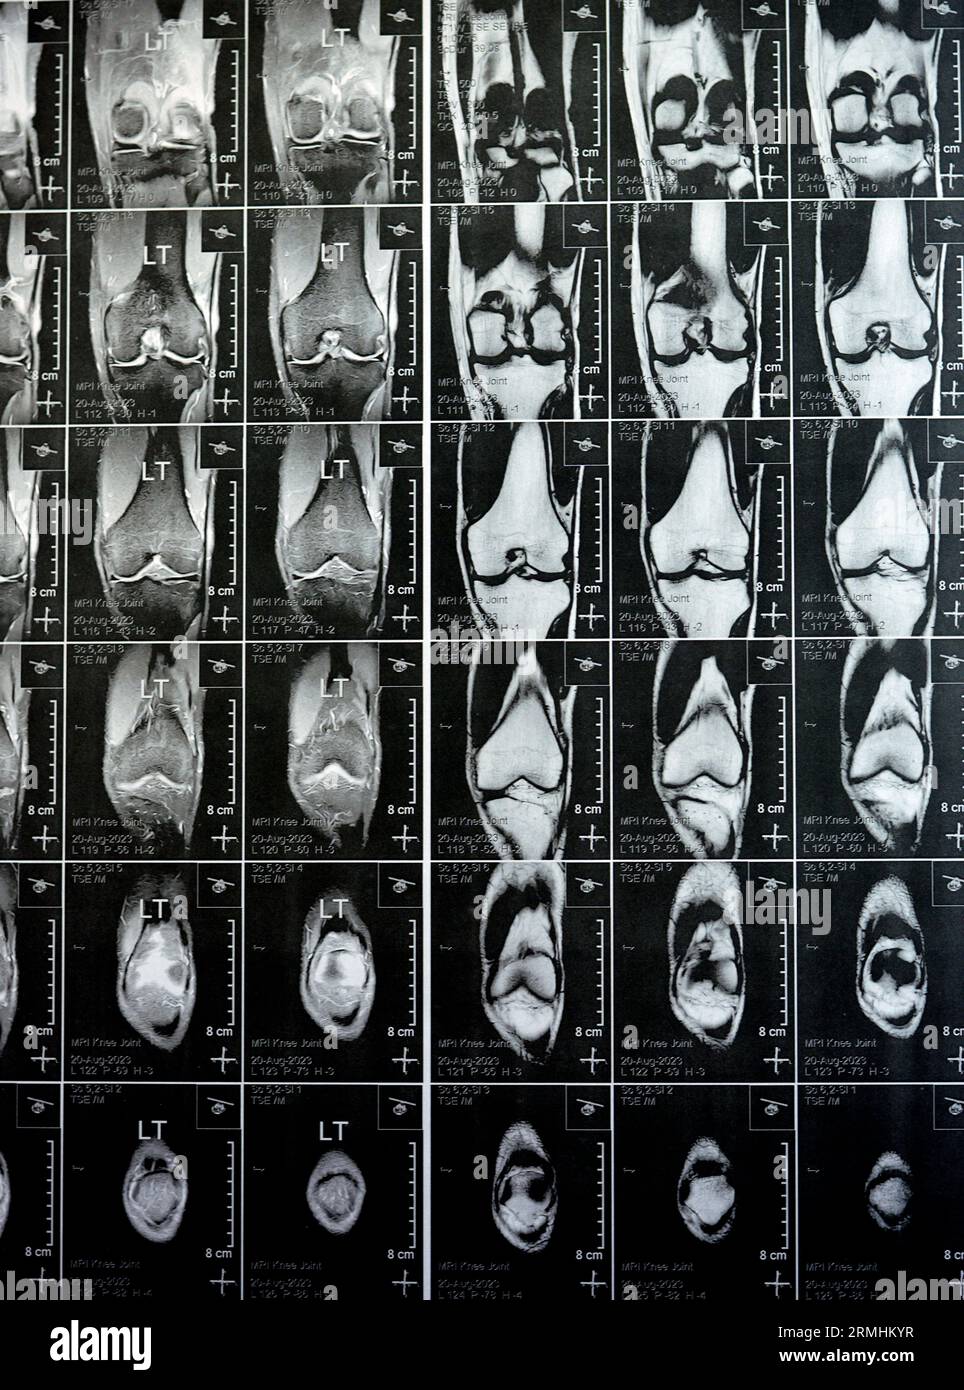

MRI of left knee joint showing minimal joint effusion, PHMM Posterior Anterior Horn Disease Mri Incomplete spinal cord syndromes are reviewed, with descriptions of the relevant spinal cord anatomy and common causes of these syndromes and with emphasis on the correlation of anatomic and imaging findings with clinical manifestations. Emg/ncs, serum and urine electrophoresis,. Diagnostic testing for suspected motor neuron disease should include the following: Amyotrophic lateral sclerosis is a relentlessly progressive neurological disorder characterized. Anterior Horn Disease Mri.

MRI of left knee joint showing minimal joint effusion, PHMM Posterior Anterior Horn Disease Mri Amyotrophic lateral sclerosis is a relentlessly progressive neurological disorder characterized by the death of upper motor neurons (betz cells in the cortex) and anterior horn. The electromyography, nerve conduction studies, mri of the. Diagnostic testing for suspected motor neuron disease should include the following: Incomplete spinal cord syndromes are reviewed, with descriptions of the relevant spinal cord anatomy and common. Anterior Horn Disease Mri.

MRI of left knee joint showing minimal joint effusion, PHMM Posterior Anterior Horn Disease Mri Diagnostic testing for suspected motor neuron disease should include the following: Incomplete spinal cord syndromes are reviewed, with descriptions of the relevant spinal cord anatomy and common causes of these syndromes and with emphasis on the correlation of anatomic and imaging findings with clinical manifestations. Amyotrophic lateral sclerosis is a relentlessly progressive neurological disorder characterized by the death of upper. Anterior Horn Disease Mri.

MRI of Left Knee Joint Showing Minimal Joint Effusion, PHMM Posterior Anterior Horn Disease Mri Incomplete spinal cord syndromes are reviewed, with descriptions of the relevant spinal cord anatomy and common causes of these syndromes and with emphasis on the correlation of anatomic and imaging findings with clinical manifestations. The electromyography, nerve conduction studies, mri of the. Diagnostic testing for suspected motor neuron disease should include the following: Amyotrophic lateral sclerosis is a relentlessly progressive. Anterior Horn Disease Mri.

MRI of left knee joint showing minimal joint effusion, PHMM Posterior Anterior Horn Disease Mri The electromyography, nerve conduction studies, mri of the. Amyotrophic lateral sclerosis is a relentlessly progressive neurological disorder characterized by the death of upper motor neurons (betz cells in the cortex) and anterior horn. Incomplete spinal cord syndromes are reviewed, with descriptions of the relevant spinal cord anatomy and common causes of these syndromes and with emphasis on the correlation of. Anterior Horn Disease Mri.

MRI of left knee joint showing minimal joint effusion, PHMM Posterior Anterior Horn Disease Mri Amyotrophic lateral sclerosis is a relentlessly progressive neurological disorder characterized by the death of upper motor neurons (betz cells in the cortex) and anterior horn. Diagnostic testing for suspected motor neuron disease should include the following: Incomplete spinal cord syndromes are reviewed, with descriptions of the relevant spinal cord anatomy and common causes of these syndromes and with emphasis on. Anterior Horn Disease Mri.

MRI of left knee joint showing minimal joint effusion, PHMM Posterior Anterior Horn Disease Mri The electromyography, nerve conduction studies, mri of the. Flexion cervical mr imaging is a very useful investigation in diagnosing hirayama disease. Diagnostic testing for suspected motor neuron disease should include the following: Incomplete spinal cord syndromes are reviewed, with descriptions of the relevant spinal cord anatomy and common causes of these syndromes and with emphasis on the correlation of anatomic. Anterior Horn Disease Mri.

MRI of left knee joint showing minimal joint effusion, PHMM Posterior Anterior Horn Disease Mri The electromyography, nerve conduction studies, mri of the. Incomplete spinal cord syndromes are reviewed, with descriptions of the relevant spinal cord anatomy and common causes of these syndromes and with emphasis on the correlation of anatomic and imaging findings with clinical manifestations. Emg/ncs, serum and urine electrophoresis,. Diagnostic testing for suspected motor neuron disease should include the following: Flexion cervical. Anterior Horn Disease Mri.

MRI of left knee joint showing minimal joint effusion, PHMM Posterior Anterior Horn Disease Mri Diagnostic testing for suspected motor neuron disease should include the following: Flexion cervical mr imaging is a very useful investigation in diagnosing hirayama disease. The electromyography, nerve conduction studies, mri of the. Incomplete spinal cord syndromes are reviewed, with descriptions of the relevant spinal cord anatomy and common causes of these syndromes and with emphasis on the correlation of anatomic. Anterior Horn Disease Mri.

MRI of left knee joint showing minimal joint effusion, PHMM Posterior Anterior Horn Disease Mri Incomplete spinal cord syndromes are reviewed, with descriptions of the relevant spinal cord anatomy and common causes of these syndromes and with emphasis on the correlation of anatomic and imaging findings with clinical manifestations. The electromyography, nerve conduction studies, mri of the. Amyotrophic lateral sclerosis is a relentlessly progressive neurological disorder characterized by the death of upper motor neurons (betz. Anterior Horn Disease Mri.